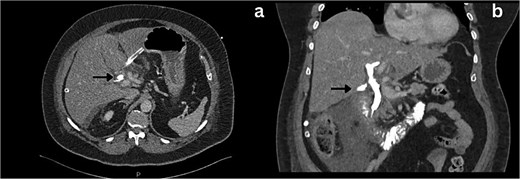

She was admitted, resuscitated, and started on intravenous antibiotics. Considering her previous history of cholecystectomy and deranged Liver Function Tests (LFTs), a clinical diagnosis of cholangitis was made. Magnetic retrograde cholangio-pancreatography (MRCP) was done, which showed significant dilatation of the biliary system extending down to the ampulla with the common hepatic duct (CHD) diameter of 23 mm with a normal pancreatic duct. Additionally, there was florid upper abdominal edema and fluid tracking along the right paracolic gutter (Fig. 1). There was no evidence of any common bile duct (CBD) stone or lesion to explain this dilatation. To further explore the underlying cause, a computed tomography (CT) pancreas was performed, which revealed no signs of pancreatitis nor any distal CBD or pancreatic lesions. The presence of fluid in the subhepatic and right paracolic regions likely indicated a bile leak (Fig. 2), but fluid related to pancreatitis could not be excluded. The findings were deliberated upon with the specialist hepatopancreaticobiliary (HPB) team and Specialist gastrointestinal (GI) radiologists. Despite extensive discussion and review with the radiologist, the nature of the fluid was not identified through the two imaging modalities employed. There was no obvious pancreatitis. A decision was reached to continue conservative management and opt for operative intervention in the event of clinical deterioration.

Axial section CT imaging; a) Normal pancreas with no evidence of inflammation or malignancy (arrow), b) extrahepatic biliary collection (asterisks).